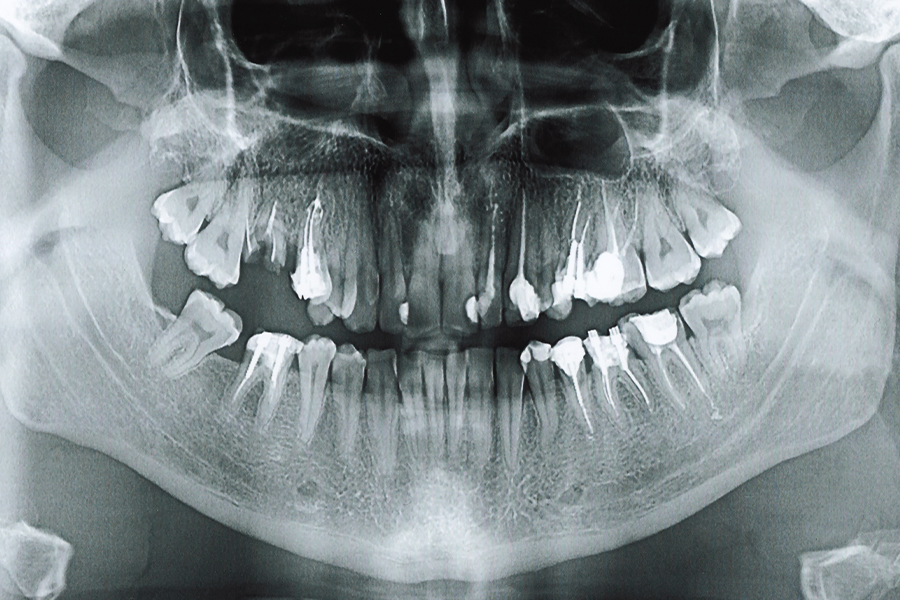

当院では先進のデジタル歯科用CTを用いることで、従来のレントゲンでは得られなかった顎の骨の立体構造や神経の位置に至るまで、詳細なデータを緻密に把握することが可能です。撮影したCTデータを専用のシミュレーションソフトで解析し、患者さまに最適な埋入位置を診断しています。

レントゲンやCT撮影、噛み合わせの検査などを行い、お口の中の状態を診査・診断いたします。精密検査の結果をもとに詳細な治療計画を立てていきます。